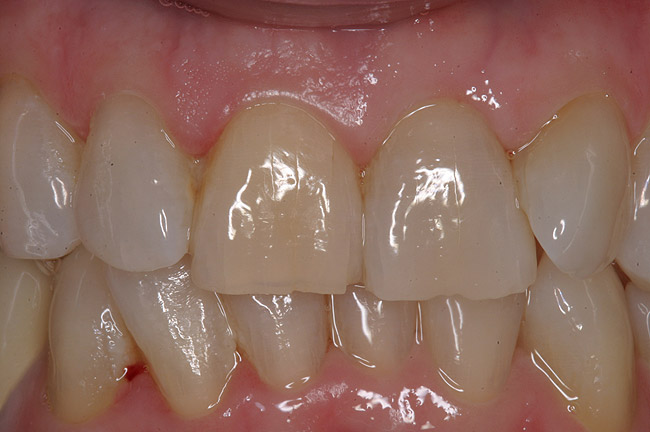

Figure 4  Final restoration of implants in the Nos. 8 and 9 sites 3 years after placement. Note the short central papilla regardless of the presence of bone. Restoration courtesy of Dr. Alan Goldberg.

Figure 4

Figure 5  A naturally low smile line hid the clinical “black triangle” from view.

Figure 5